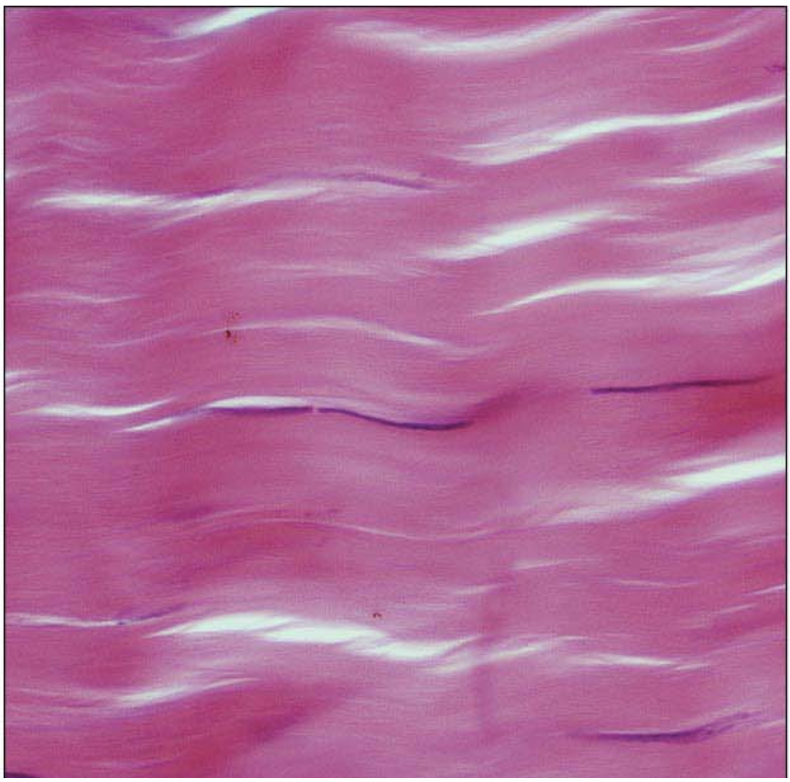

Dense Regular CT

Dense Irregular CT